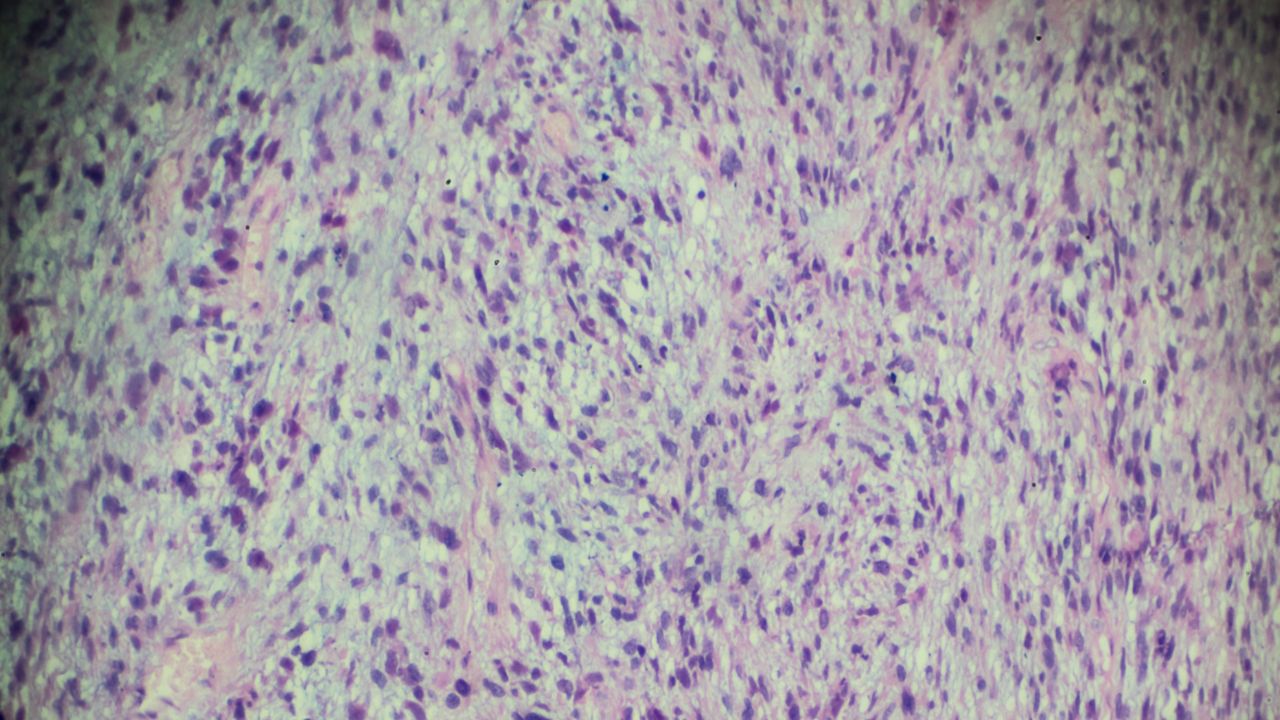

تشخیص قطعی تنها با بیوپسی امکانپذیر است. در این مرحله، نمونهای از بافت تومور از طریق سوزن یا جراحی برداشته میشود تا بررسی شود. نمونه برداشتشده تحت آنالیز پاتولوژی و ایمونوهیستوشیمی قرار میگیرد و وجود مارکرهای اختصاصی عضلانی مانند میوژنین و دسمین بررسی میشوند.

در برخی موارد، برای تمایز دقیق بین انواع مختلف رابدومیوسارکوم، آزمایشهای مولکولی و ژنتیکی انجام میشود. همچنین در صورت شک به گسترش بیماری، آسپیراسیون و بیوپسی مغز استخوان لازم است.